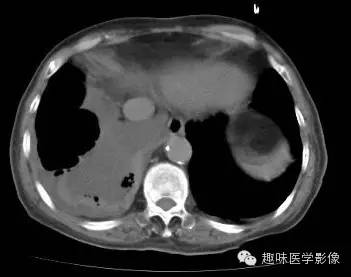

男,71岁,发热待查。

双肺多发无壁低密度区,以右肺下叶底部为主。右肺下叶见大片不规则实变阴影伴多发空洞影,实变肺组织内见支气管气象,右肺下叶支气管局部显示不清。纵隔内见淋巴结。右侧胸腔内见积液影,邻近胸膜肥厚。主动脉、冠状动脉钙化。

右肺下叶肺脓肿、肺炎伴胸腔积液,肺气肿、肺大泡。

右胸廓变小,心影右移;右肺下叶多房性空洞,空洞内未见明显液平面,右下肺病变应该是下叶阻塞性肺炎,实变肺组织内见支气管气像,邻近胸膜增厚,并合并胸腔积液,支持肺脓肿。